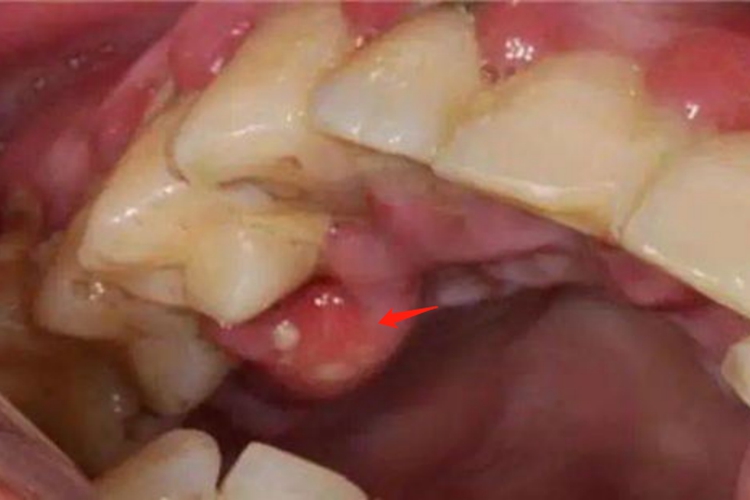

急性牙周脓肿可在患牙的唇颊侧或舌腭侧肿胀突起,形成一个红色的泡,牙龈发红、水肿、表面光亮,脓肿早期疼痛较剧烈,可有搏动疼痛,病人自觉患牙有浮起感。

黏膜类天疱疮的早期,可在牙龈缘及附着龈处局部充血发红,其上形成直径为2-6mm的水疱,疱液清亮或呈血疱,表现为一个红色的泡。破溃后可见白色或灰白色的疱膜。除牙龈外,硬腭和颊部的咀嚼黏膜也常受累。